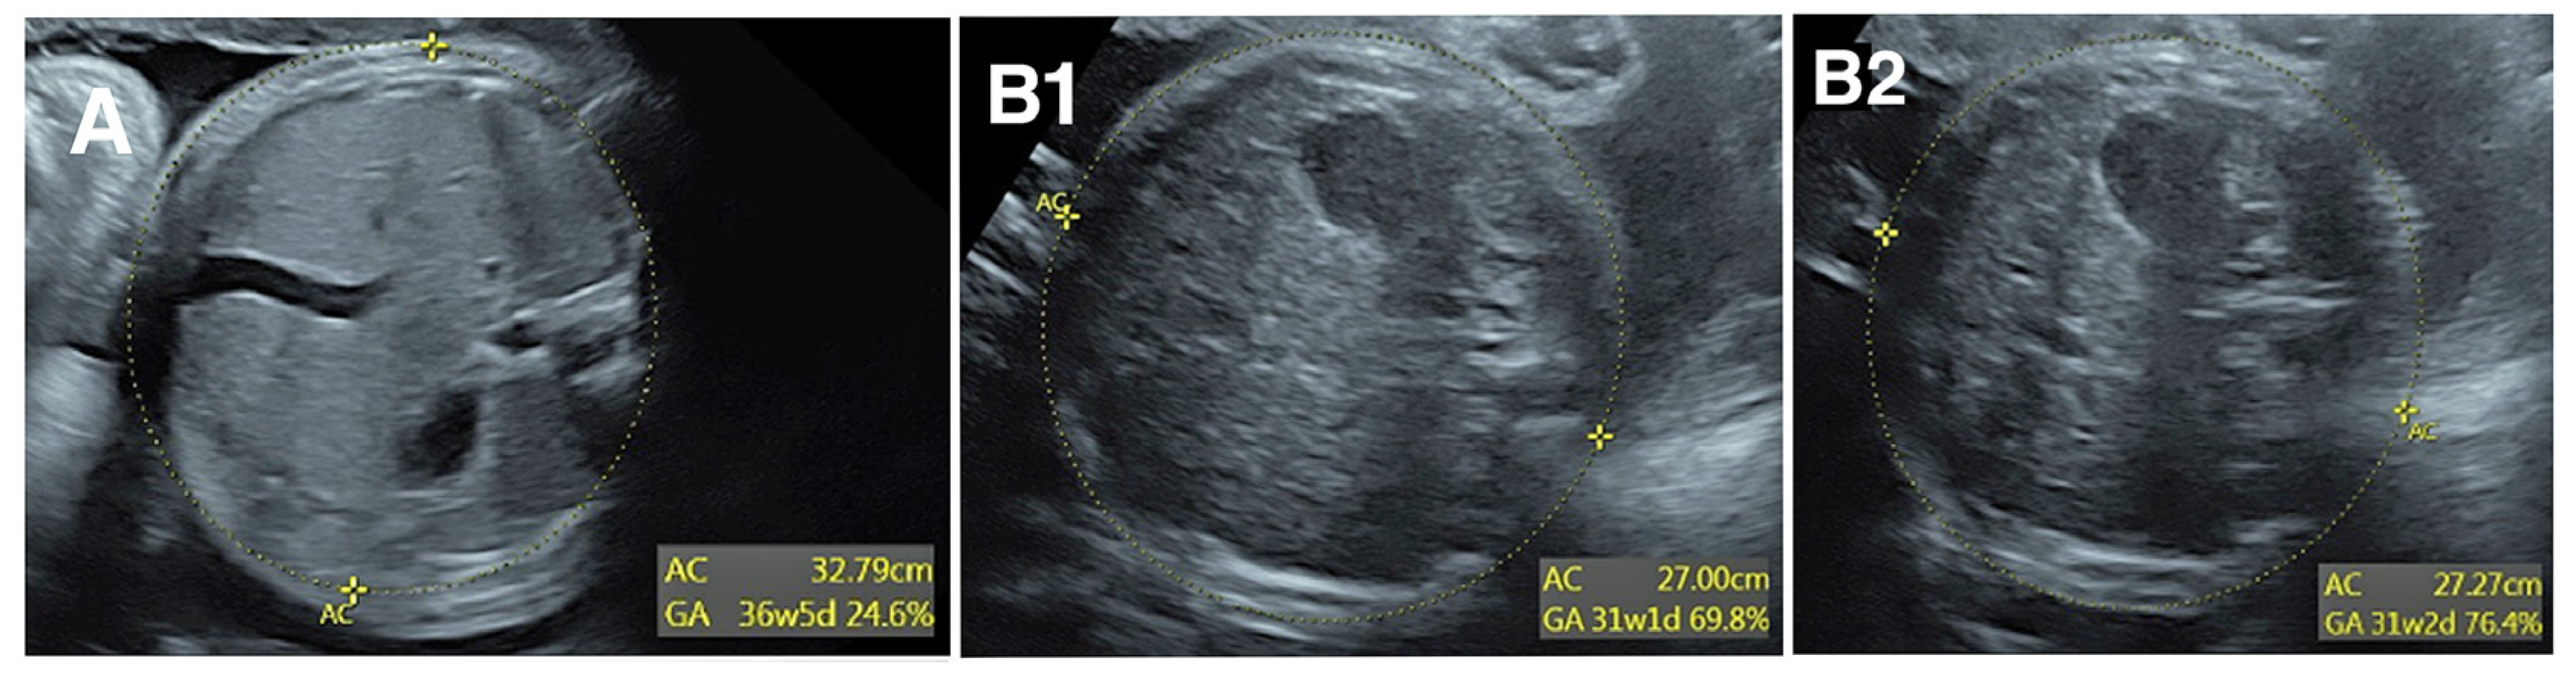

The interpreting physician is the first step in detecting and correcting measurement error, but this first level review does not prevent all errors. Consider the 3 images of AC in Figure 1. In panel A, the calipers are placed far inside the fetal abdomen, so AC is clearly undermeasured. Though few providers would find this image acceptable, it was obtained in a very busy ultrasound practice and the measurement error was not detected by the sonographer or the reading physician. Panels B1 and B2 show two images from a different fetus taken a few seconds apart. An important limitation is how difficult it is to see the ellipses measuring AC. Notwithstanding that difficulty, the difference in AC between panels B1 and B2 is 2.7 mm or 1%, with AC slightly undermeasured in panel B1. Although this might seem inconsequential, the standard deviation (SD) of AC is 13.4 mm per Hadlock et al. [12], so 2.7 mm is 0.2 SD. If a sonographer systematically undermeasures AC by 0.2 SD, they will find AC <10th percentile in 14% of exams rather than the expected 10%. This would result in a 40% overdiagnosis of fetal growth restriction, which in turn would result in excess costs of fetal surveillance, repeat exams, and patient anxiety. Yet a systematic undermeasurement of this magnitude would probably go undetected.

Another consideration is that high numbers of exams can result in very low P-values even with very small differences in z-score, that is differences may be statistically significant even though they are too small to be clinically relevant or indeed, too small to be detected by image audit. Figure 1, Panels B & C shows an example of how difficult it is to see differences in AC of 0.2 SD, corresponding to differences in z-score of 0.2. As a “rule-of-thumb”, we find that image audits are generally not useful unless a sonographer’s z-score differs from the practice mean by at least 0.3. This criterion was met for sonographers 1, 2, and 8 in Table 1.

Figure 1. Abdominal circumference (AC) measurements shown by yellow dotted ellipses. In panel A, AC is clearly undermeasured. In panels B1 and B2, the difference in AC is only 1% but systematic differences of this magnitude can be clinically relevant.